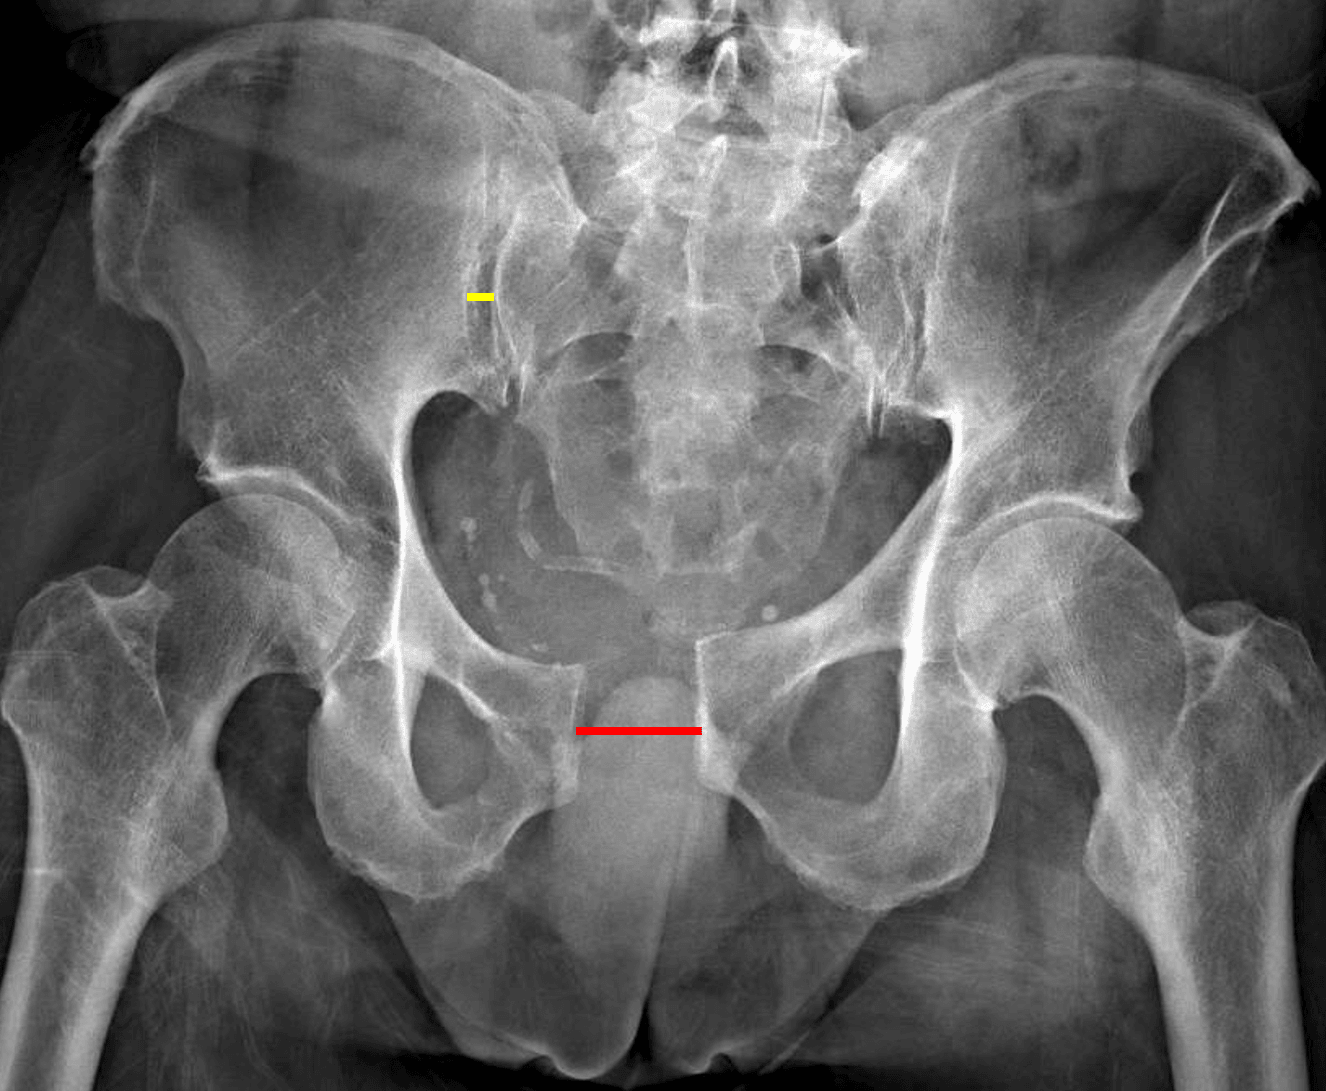

APC II unstable pelvic ring injury with widening of the pubic symphysis (red line) and anterior right sacroiliac joint (yellow line).

Unstable pelvic ring injury with diastasis of the pubic symphysis measuring up to 3 cm and mild widening of the right sacroiliac joint.

Unstable pelvic ring injury (APC II)